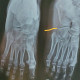

Perempuan 29 tahun nyeri pada kaki dan bengkak setelah cedera menendang pintu.

Hasil Xray sebagai berikut.

Temuan apa yang sejawat lihat?

Anjuran tata laksana?

Tampak fraktur metatarsal, ya Dok?